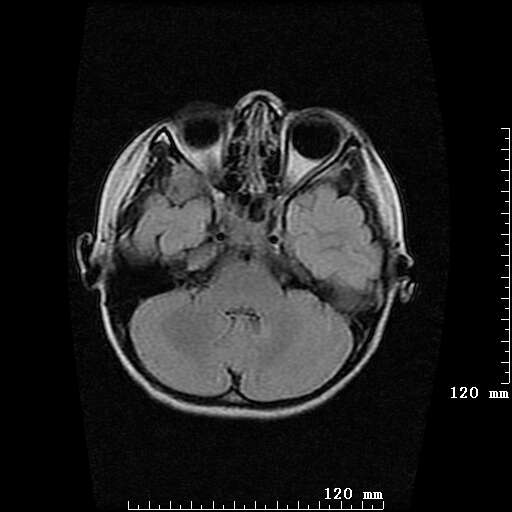

女,7岁,三岁才说话、走路。现智力尚可,走路不稳。临床怀疑大脑发育不全。

脑折质变薄,双侧侧脑室稍扩张,支持考虑脑折质发育不良

侧脑室周围白质软化症。

侧脑室周围白质数量减少,侧脑室不对称性扩大,左侧侧脑室后角呈方形改变,脑沟加深,结合临床考虑脑室周围白质软化症(pvl)。期待结果!